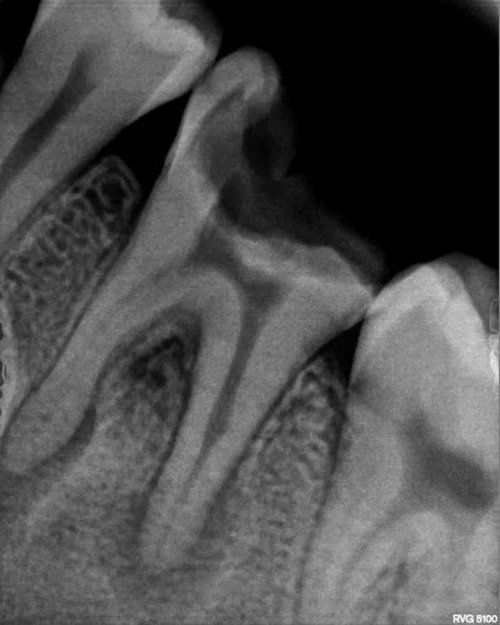

1、診斷問題。要詳細(xì)詢問主訴牙的既往史、現(xiàn)病史,做出更確切的診斷,不要忽略其一,做到有所為,有所不為。比如本是中深齲中的可復(fù)性牙髓炎,需先進(jìn)行安撫后再充填,不宜一次性充填。需對(duì)癥下藥,不要抱有僥幸的心理。

2、備洞問題。診斷已有確切,接下來備洞。盡使用新的車針,并大量手機(jī)冷切水,間歇性去腐。操作輕柔,近髓處腐質(zhì)盡量使用慢機(jī)或小挖匙,盡減少備洞時(shí)溫度對(duì)牙髓的刺激因素,同時(shí)對(duì)于洞邊緣的無基釉或薄壁弱尖要有效的去除,預(yù)防白線和樹脂的塌陷而引起微滲漏。

3、繼發(fā)齲問題。腐質(zhì),沒有去凈,建議使用齲顯式劑。這個(gè)問題應(yīng)引起關(guān)注。